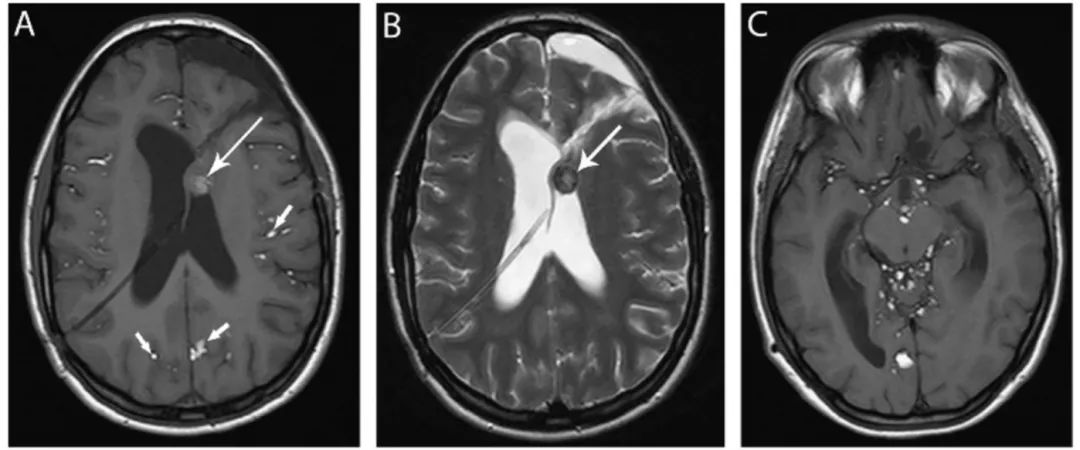

图8 脉络丛囊肿

FLAIR像(A)和DWI像(B)显示双侧脑室内脉络丛囊肿(箭头),并在DWI像上表现为特征性的高信号。

图9 室管膜囊肿

轴位T2WI像显示一个大的脑室内囊肿,等CSF信号,引起右侧侧脑室扩张,可见囊壁(箭头)。

图10 胶样囊肿

轴位T2WI(A)和T1WI(B)显示第三脑室入口水平一个圆形边界清晰的囊肿(箭头),表现为典型的T2低信号和T1高信号。